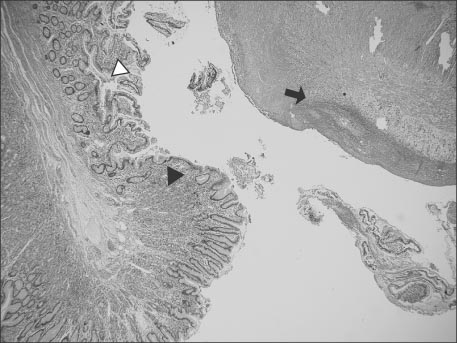

Fig. 5

White arrowhead indicates intestinal tissue; Black arrowhead indicates gastric tissue; Black arrow indicates serosa tissue and inflammation (H&E, ×40).

Fig. 5 White arrowhead indicates intestinal tissue; Black arrowhead indicates gastric tissue; Black arrow indicates serosa tissue and inflammation (H&E, ×40).